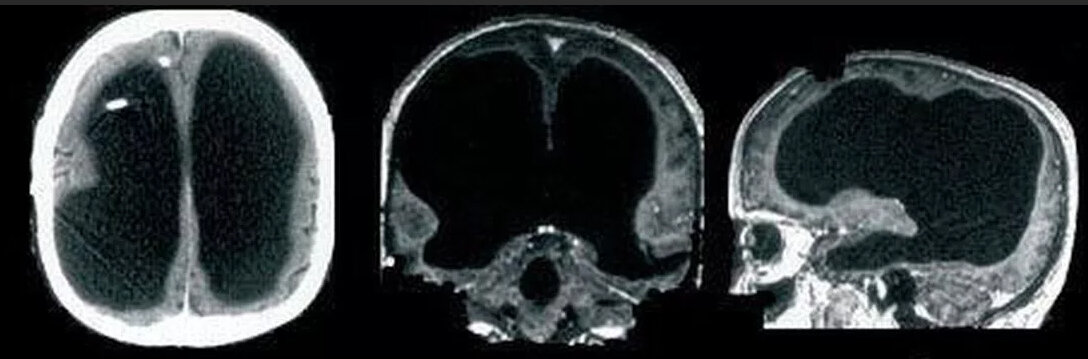

44-летний мужчина из Франции (чью личность врачи так же не стали раскрывать) дожил до своих лет имея мозг размером с котлету!

Парень пришел в клинику с жалобой на слабость в левой ноге. Естественно её связали с мозгом, но до сканирования его головы никто и не подозревал, что 90 % черепа наполняла жидкость. Наверно этот человек должен был быть очень глупым и заторможенным, но нет. Его iq составлял 75 и это не мешало ему работать госслужащим не испытывая никаких проблем.

У мужчины был редкий случай гидроцефалии, но вместо расширения головы его мозг сжимался. Год за годом жидкость спрессовывала мозг увеличивая его плотность.

Долгие годы врачи строили и строят теории по этому поводу. Но удалось сделать вывод, что наш мозг способен перестраиваться под какие-либо повреждения и если проблемы возникли еще в детском возрасте, то никаких осложнений даже заметно не будет.